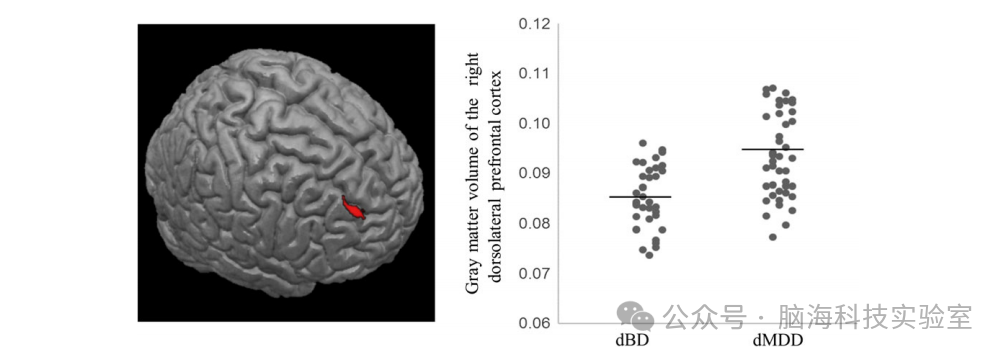

在美国独立样本中,dBD患者相较于dMDD患者在右DLPFC的灰质体积显著减少(x=25.5, y=51, z=34.5;k=64;t=3.36;校正后P值=0.03)。dBD患者与健康对照相比,在左侧内侧眶额回和上内侧额回区域(x=12, y=55.5, z=-1.5;k=387;t=3.54;未校正P值=0.0002)的灰质体积减少,但未达到多重比较校正后的显著性水平。dMDD患者与健康对照之间在美国样本的VBM分析中未发现显著的区域灰质体积差异。

图3:独立第二队列中基于体素的形态计量学分析结果。